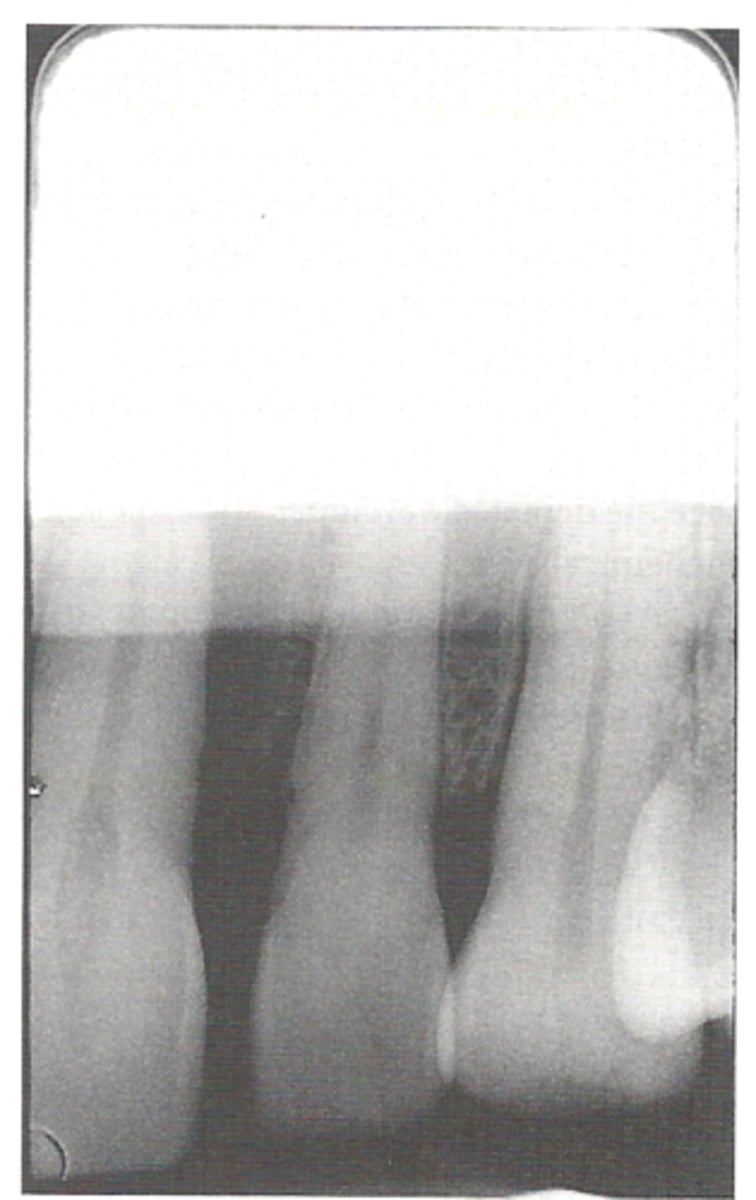

Foreshortened Images

The vertical angulation was excessive, or too steep, and as a result images are shorter than the actual teeth

<p>The vertical angulation was excessive, or too steep, and as a result images are shorter than the actual teeth</p>